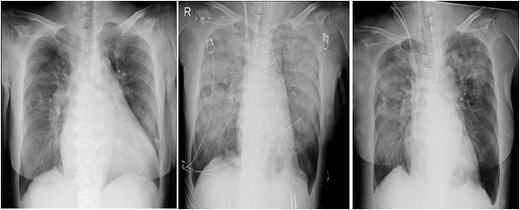

Post-operative CXR showed unilateral consolidation (Fig. 2). Re-expansion pulmonary edema was suspected. Mechanical ventilation with a high PEEP of 12–14 cmH2O and a peak inspiratory pressure of 30 cmH2O was provided; nonetheless, there was no improvement in the respiratory condition, resulting in hypercapnia and severe acidosis with a pH of 7.06 and pCO2 of 94.4 mmHg. Thus, VV-ECMO was immediately initiated after placing a 21 Fr drainage cannula in the right atrium through the right femoral vein and a 15 Fr return cannula through the left femoral vein under fluoroscopic guidance. Unfractionated heparin was used for anticoagulation with a target ACT of 150 s, while being concerned about the risk of bleeding from the surgical site.

Chest radiographs obtained pre-operation (left), post-operation (middle) and 2 days post-operatively (right).

Two days post-operatively, VV-ECMO was terminated due to improvement in respiratory function, hypercapnia and acidosis. The amount of sputum also decreased remarkably with PEEP at 12 cmH2O. The ECMO duration was 41 h. Mechanical ventilatory support was terminated on POD 9. The patient was discharged on POD 48.